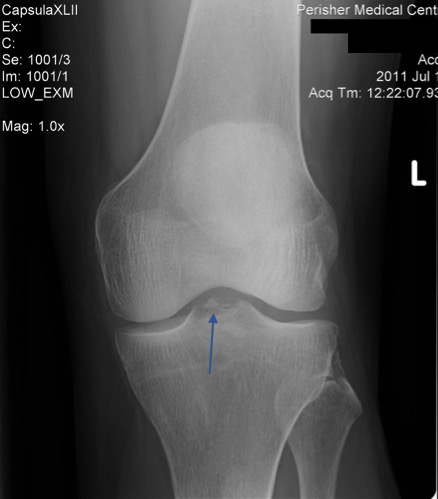

Lesson 1 / A knee that swells up quickly after an injury contains a haemarthrosis. It’s full of blood and is therefore a fracture until proven otherwise, in which case it is then probably an ACL rupture. X-rays are mandatory.

A haemarthrosis results from bleeding into the joint. The quicker the swelling, the more bleeding and therefore any fracture will be bigger and/or more displaced. Fractures that bleed into the joint are tibial plateau/spine fractures, femoral condyle fractures, and patella fractures. An ACL will also cause a haemarthrosis, though this may take longer to develop and typically will not be present when you first see the patient.

You don’t want to go wiggling a knee that has a tibial plateau fracture (as in the x-ray below) going on inside it. Indeed, if the x-rays show a fracture – bingo – job done. Sometimes though, plateau fractures are not well defined on x-ray, so follow up with CT. If there isn’t a fracture then go ahead and examine the patient.

If you think the ACL has gone, then you need to x-ray to rule out a tibial spine fracture as in the x-ray below. This is critical because ACL injuries should be mobilised early with aggressive physiotherapy prior to reconstruction, whereas the fracture should be immobilised and non-weight bearing on crutches prior to definitive imaging and orthopaedic review. Important difference.